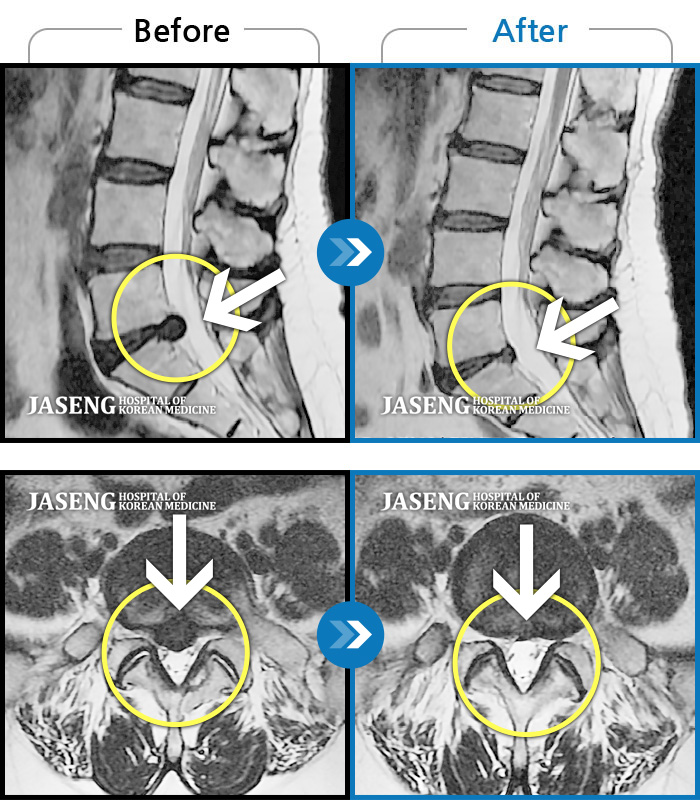

허리디스크

잠실 · 한상욱 원장

우측 엉치부터 우측 다리부터 발끝까지 저리고 아프다. 감각까지 먹먹하다.

촬영시기

2022.04.15 ~ 2022.10.22

2022.12.02